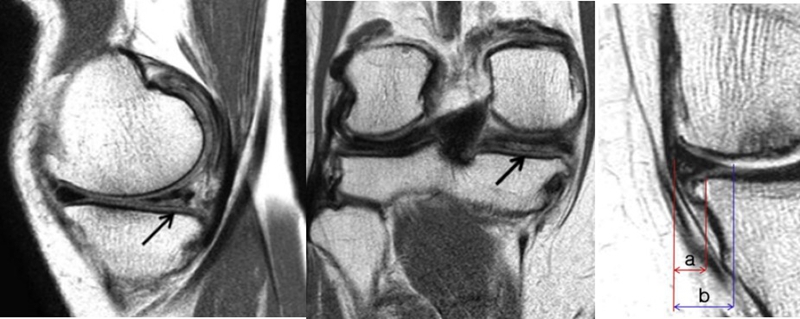

SONK与内侧半月板后根部损伤,有国外学者在SONK患者中通过MRI及关节镜检查,常可发现合并内侧半月板后根部的撕裂,该发生率可达到80%(24/30), 15例完全撕裂,9例部分撕裂。结果表明SONK可能与内侧半月板后根部撕裂后,导致股骨负重区的应力集中、软骨下骨髓水肿有关。

膝内翻 内侧半月板根部撕裂

应力源性理论

内侧半月板挤压(MME)以绝对值和挤压相对百分比 (RPE) 的形式呈现,其定义为挤压半月板宽度与整个半月板宽度相比的百分比